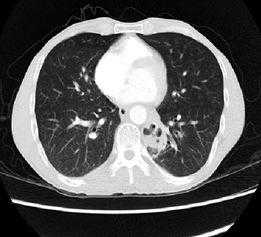

胸部CT扫描检查无痛苦、创伤小,是目前临床上常用的诊断手段。由于低分辨率平扫不能显示异常血管,难以与其他相关疾病鉴别,导致误诊率高,因此,临床上如怀疑肺隔离症,应予以行胸部增强CT+CTA,以准确发现异常滋养血管。

它可以长成这样↓↓↓

图7左下肺内侧基底段团状密度增高影,内可见不规则含气空腔及气液平

也可以仅仅长成这样↓↓↓

图8双肺下叶见少量絮状、磨玻璃样稍,高密度影,边缘模糊